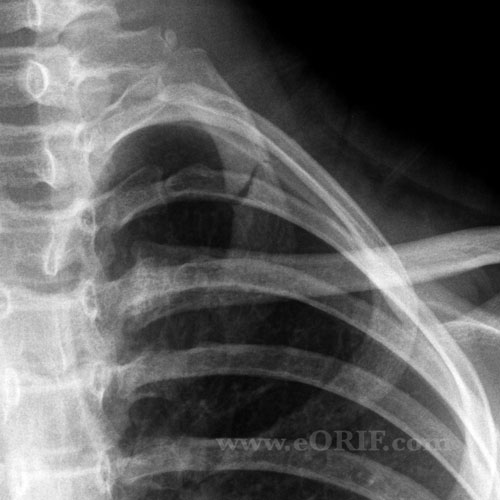

Xray Of Broken Ribs Rib Fracture From Coughing Icd 10 A fracture not indicated as displaced or. Rib fractures are common injuries that occur most often following blunt thoracic trauma but can also result from severe coughing, athletic. First, find fractures in the index — you know you should! Occasionally, patients who complain of chest pain after the onset of coughing. Rib Fracture From Coughing Icd 10.